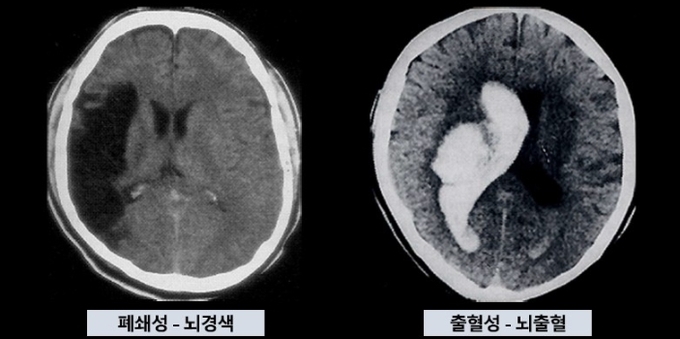

서울아산병원에 따르면 대부분의 뇌 질환으로 인해 손상된 신경세포는 쉽게 회복되지 않아 이에 대한 조기 진단과 질병 활성도에 대한 모니터링이 중요하다.